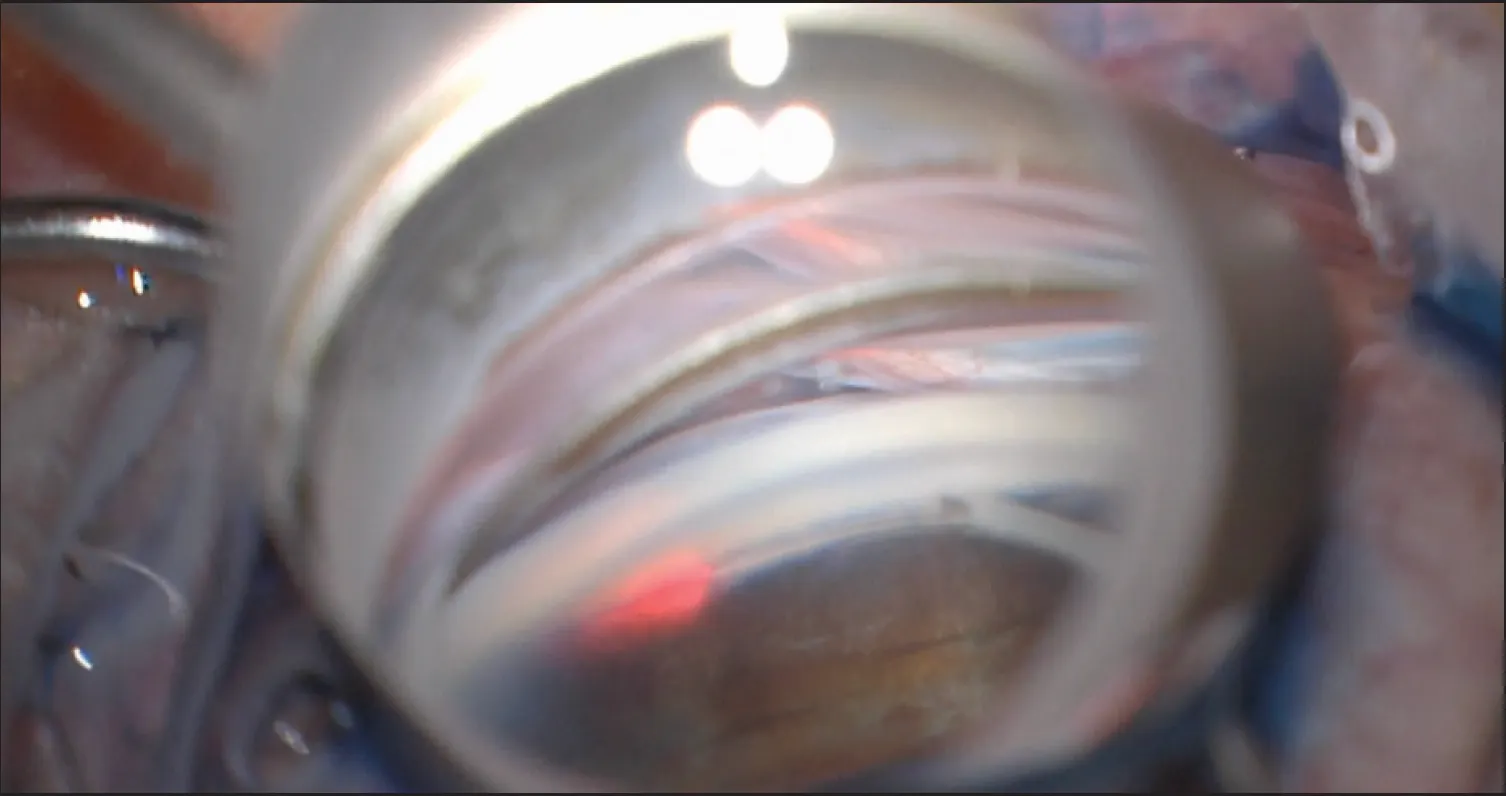

A defining feature of MYOC-associated JOAG is that the pathology has been shown to be within the TM and no other tissue. As such, TM-specific surgeries, especially GATT, are uniquely effective for the treatment of MYOC-associated JOAG (Figure). Studies evaluating GATT in patients with known MYOC variants have demonstrated the procedure’s remarkable success; GATT lowered IOP by a mean of 26 mm Hg (68%) and decreased the medication burden from an average of 3.8 medication classes to zero.1,22

Figure. Intraoperative photograph of GATT using an iTrack Advance lighted microcatheter (Nova Eye Medical), an effective surgical approach in MYOC-associated JOAG.